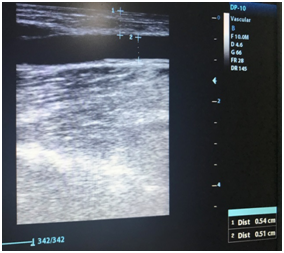

Other clinical guidelines consider an ideal AV fistula one that meets the “6” rule: no more than 6 mm deep, at least 6 mm in diameter, and with a minimum flow of 600 ml / min Figure 2.4 Maturation of non-assisted AVF is predicted by blood flow, location, depth, and stenosis of the AVF.12 However, the postoperative diameter of the venous path of the AVF has the highest predictive index of greater long-term posterior permeability Figure 3.13

Figure 2 Native arteriovenous fistula, ultrasound measurements 0.54 mm depth and diameter: 0.51 mm.